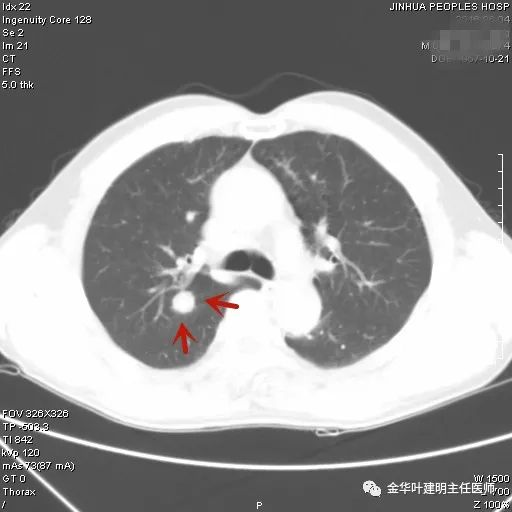

上图示浸润性腺癌典型表现。实性结节,有细毛刺征,有血管进入病灶,部分地方有浅分叶。